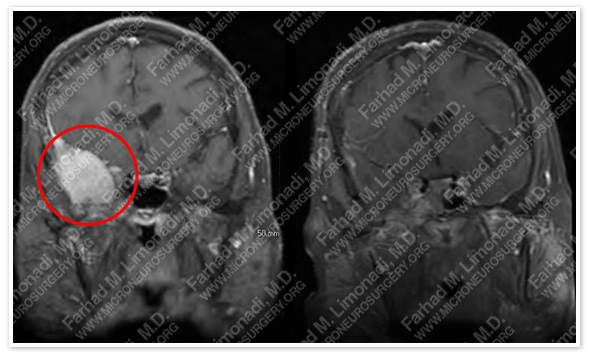

MRI scan of patient’s brain shows a sphenoid wing meningioma with intraconal extension.

Before Operation                                              After Operation